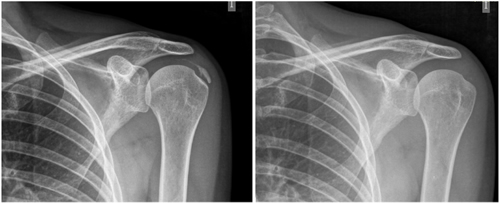

The average number of sessions in our series was 20. The criteria for continuing or stopping treatment was the radiological and clinical evolution (Figures 4 and 5). The interventions were performed up to a maximum of 40 sessions. Perrón treated patients for 9 sessions (3 weekly sessions for 3 weeks) (14). Leduc treated with 10 sessions (3 per week for the first two weeks; then one weekly for 4 weeks) (15). Rioja-Toro treated patients for 40 sessions (5 times per week) and evaluated them at 20 and 40 sessions (3). Chico-Álvarez treated patients between 15 and 30 sessions depending on the radiological evolution (5 times per week) (1).

Fig. 4. 47-year-old female patient with formative right supraspinatus calcific tendinitis who, after 30 sessions of iontophoresis, decreased pain measured by VAS from 6/10 to 3/10 and calcification from 38 mm to 8 mm (assessments at onse and at 10, 20 and 30 sessions, respectively).